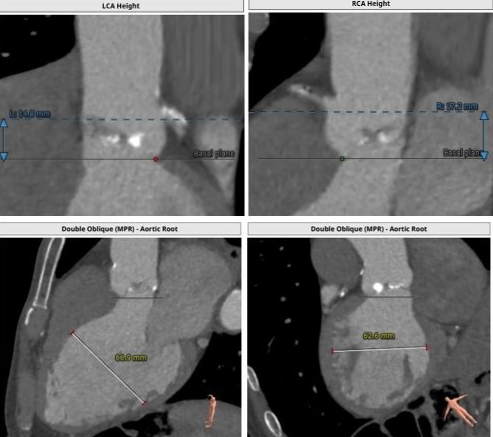

主动脉CTA:三叶瓣,瓣环面积为518 mm²,严重钙化;法式窦结构可,主动脉瓣瓣环周径82.3 mm,平均直径26.2mm,左室流出道周径28.0mm,主动脉窦管交界处(STJ)高28.9 mm;左冠高度14.8mm,右冠高度17.2mm,升主动脉未见明显增宽,主动脉根部角度44°,左室大(66.9mm),心尖部局部心肌薄弱,推荐右侧股动脉做为主入路。推荐使用26号瓣膜。